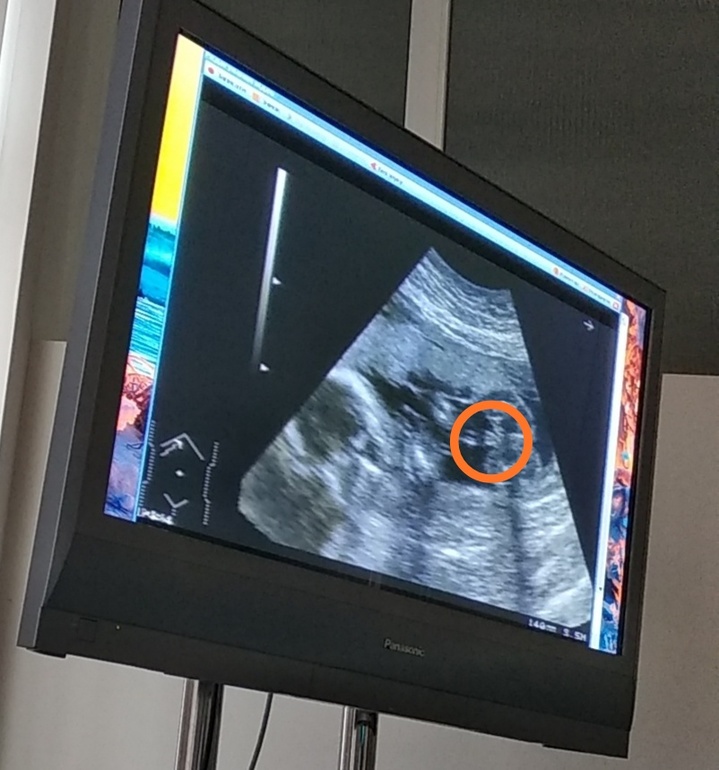

УЗИ 20 недель и пол ребенка

ЭкваторПо УЗИ ,смотрели сказали все хорошо.А на счёт пола сначала одна загадка.Врач смотрела ,но так и не дала точного результата кто ) ,а так хотелось узнать кто

.Сначала предположила один пол,потом второй.Добавлю фото обвела кружочком гениталии ребенка) .Кто хоть не много понимает подскажите.

Девочка скорей всего. Как у нас говорят, три полоски адидас 😅😂 У нас на фото так же было. На второй фотке вообще не поймёшь, что, точно не половые принадлежности, а что-то другое. Для мальчика слишком мало для такого срока.

Хмммм.....На первом фото девочка похоже, а вот второе это сынишка точно